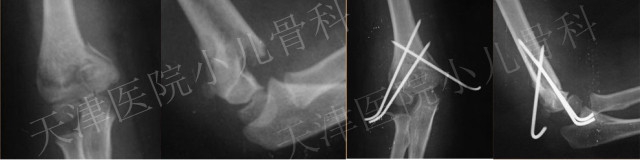

老师:早期闭合复位经皮穿针固定(CRPP)。手术复位时特别注意需要通过伸肘外翻的手法纠正尺侧塌陷,我习惯3枚克氏针内外侧交叉固定,这样多皮质的固定可以重建并维持内侧柱的长度,从而避免肘内翻的发生。